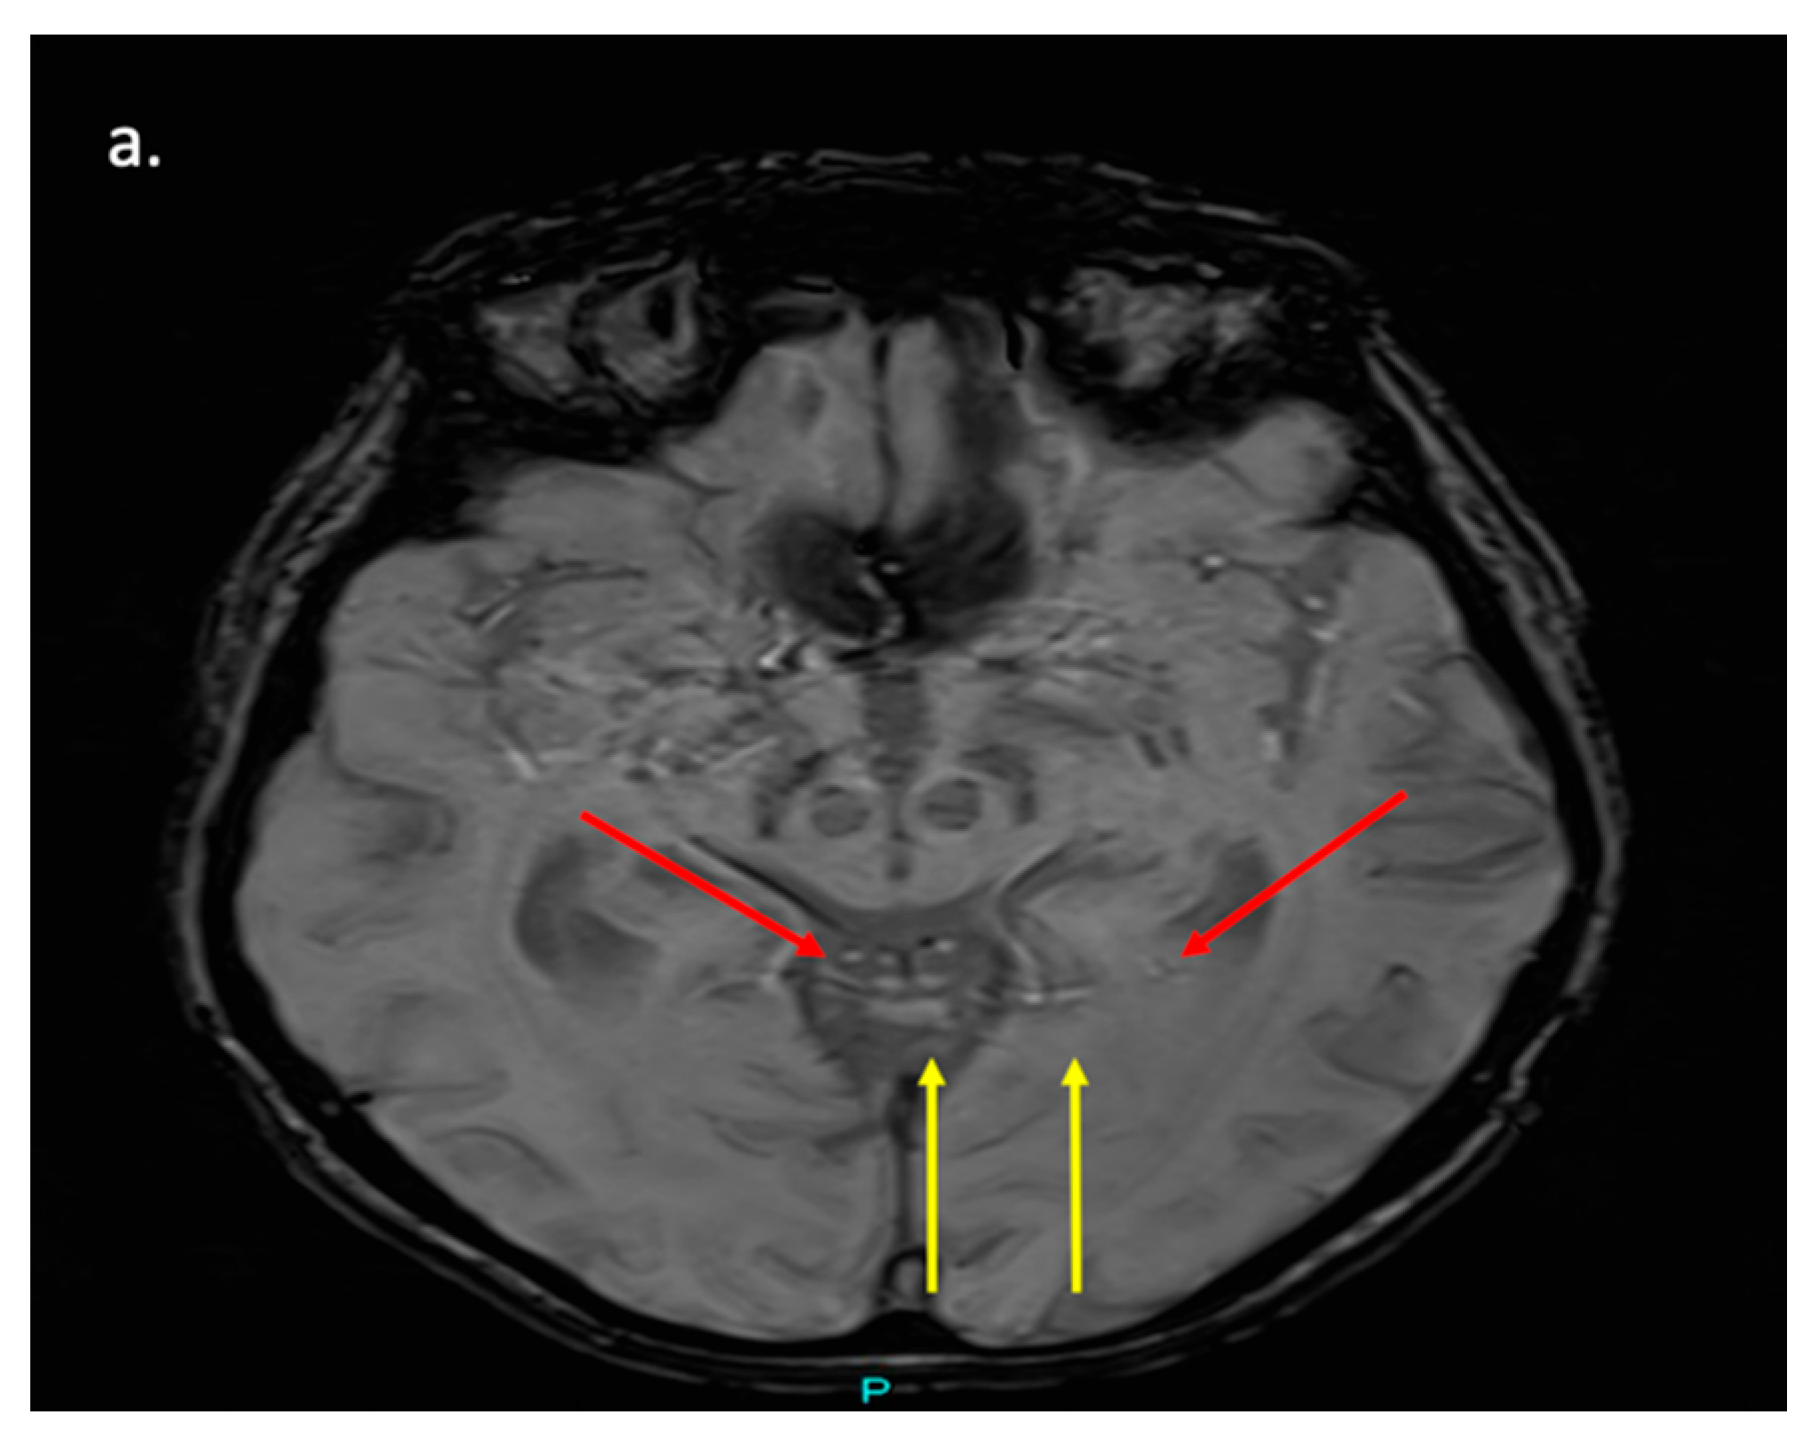

Figure 3. MRI Brain Image Highlighting Key Regions Commonly Affected in Parkinson’s Disease (PD). Axial T2*-weighted MRI at the level of the midbrain in a healthy control brain. The image demonstrates normal susceptibility-related signal dropout in the substantia nigra pars compacta (red arrows) and red nucleus (yellow arrows), reflecting typical iron deposition patterns seen in non-pathological aging.